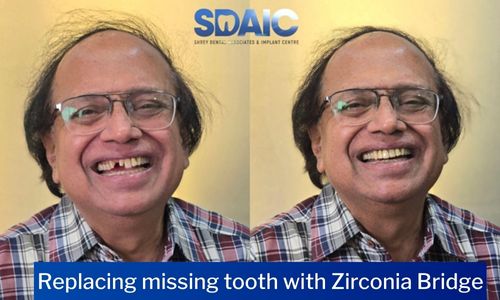

Before & After Results

See the difference expert care can make. Real treatments, real improvements, and real smiles restored with precision.